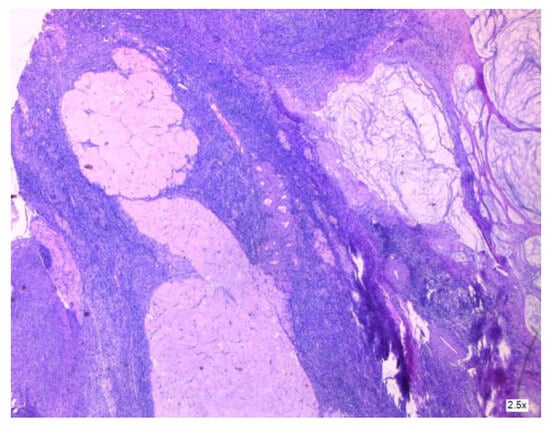

3.2.2. Clinical and Pathology Findings

3.1.4. Malignant Transformation of an Ovarian Primary Mature Cystic Teratoma (MCT)

3.1.5. Appendiceal Mucocele with Peritoneal Dissemination Mimicking an Ovarian Tumor with Peritoneal Carcinomatosis

- Ponzini, F.; Kowal, L.; Ghafoor, M.; Goldberg, A.; Chan, J.; Lamm, R.; Cannaday, S.M.; Richard, S.D.; Nevler, A.; Lavu, H.; et al. Rare occurrence of pseudomyxoma peritonei (PMP) syndrome arising from a malignant transformed ovarian primary mature cystic teratoma treated by cytoreductive surgery and HIPEC: A case report. World J. Surg. Oncol. 2022, 20, 78. [Google Scholar] [CrossRef]